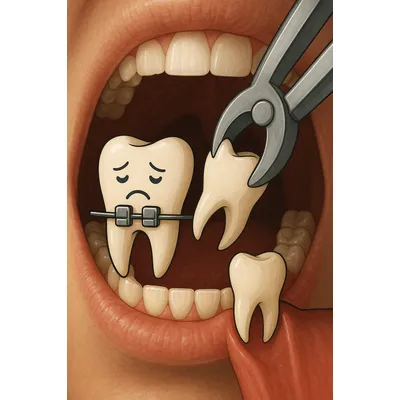

نمای واقعی درمان ارتودنسی با ابزار دندانپزشکی و اصلاح بایت

کلوزآپ واقعی ارتودنسی و رفع ازدحام دندانی با ابزار دندانپزشکی

فرآیند کشیدن دندان در ارتودنسی

کشیدن دندان در ارتودنسی یک روند کاملاً برنامهریزیشده است که با هدف فراهمکردن فضای کافی و رفع نامرتبی دندانها انجام میشود. در مرحلهی نخست، ارتودنتیست با معاینه دقیق و تصویربرداری تخصصی مانند OPG یا CBCT وضعیت فک و تراکم دندانی را بررسی میکند.

سپس با استفاده از بیحسی موضعی، شرایطی بدون درد برای بیمار ایجاد میشود. پس از آن، دندان انتخابشده توسط متخصص با دقت خارج میگردد تا فضای لازم برای حرکت دندانهای دیگر فراهم شود.

مرحلهی پایانی این فرآیند مربوط به مراقبتهای بعد از کشیدن دندان است؛ استفاده از گاز استریل برای کنترل خونریزی، مصرف داروهای تجویزشده و رعایت پرهیزهای غذایی مانند خودداری از خوردن غذاهای سفت یا نوشیدنیهای گازدار اهمیت زیادی دارد.

در مجموع، کشیدن دندان در ارتودنسی اقدامی کنترلشده و علمی است که با رعایت اصول درمان و مراقبتهای لازم، زمینهساز موفقیت در درمان ارتودنسی و دستیابی به لبخندی متناسب خواهد بود.